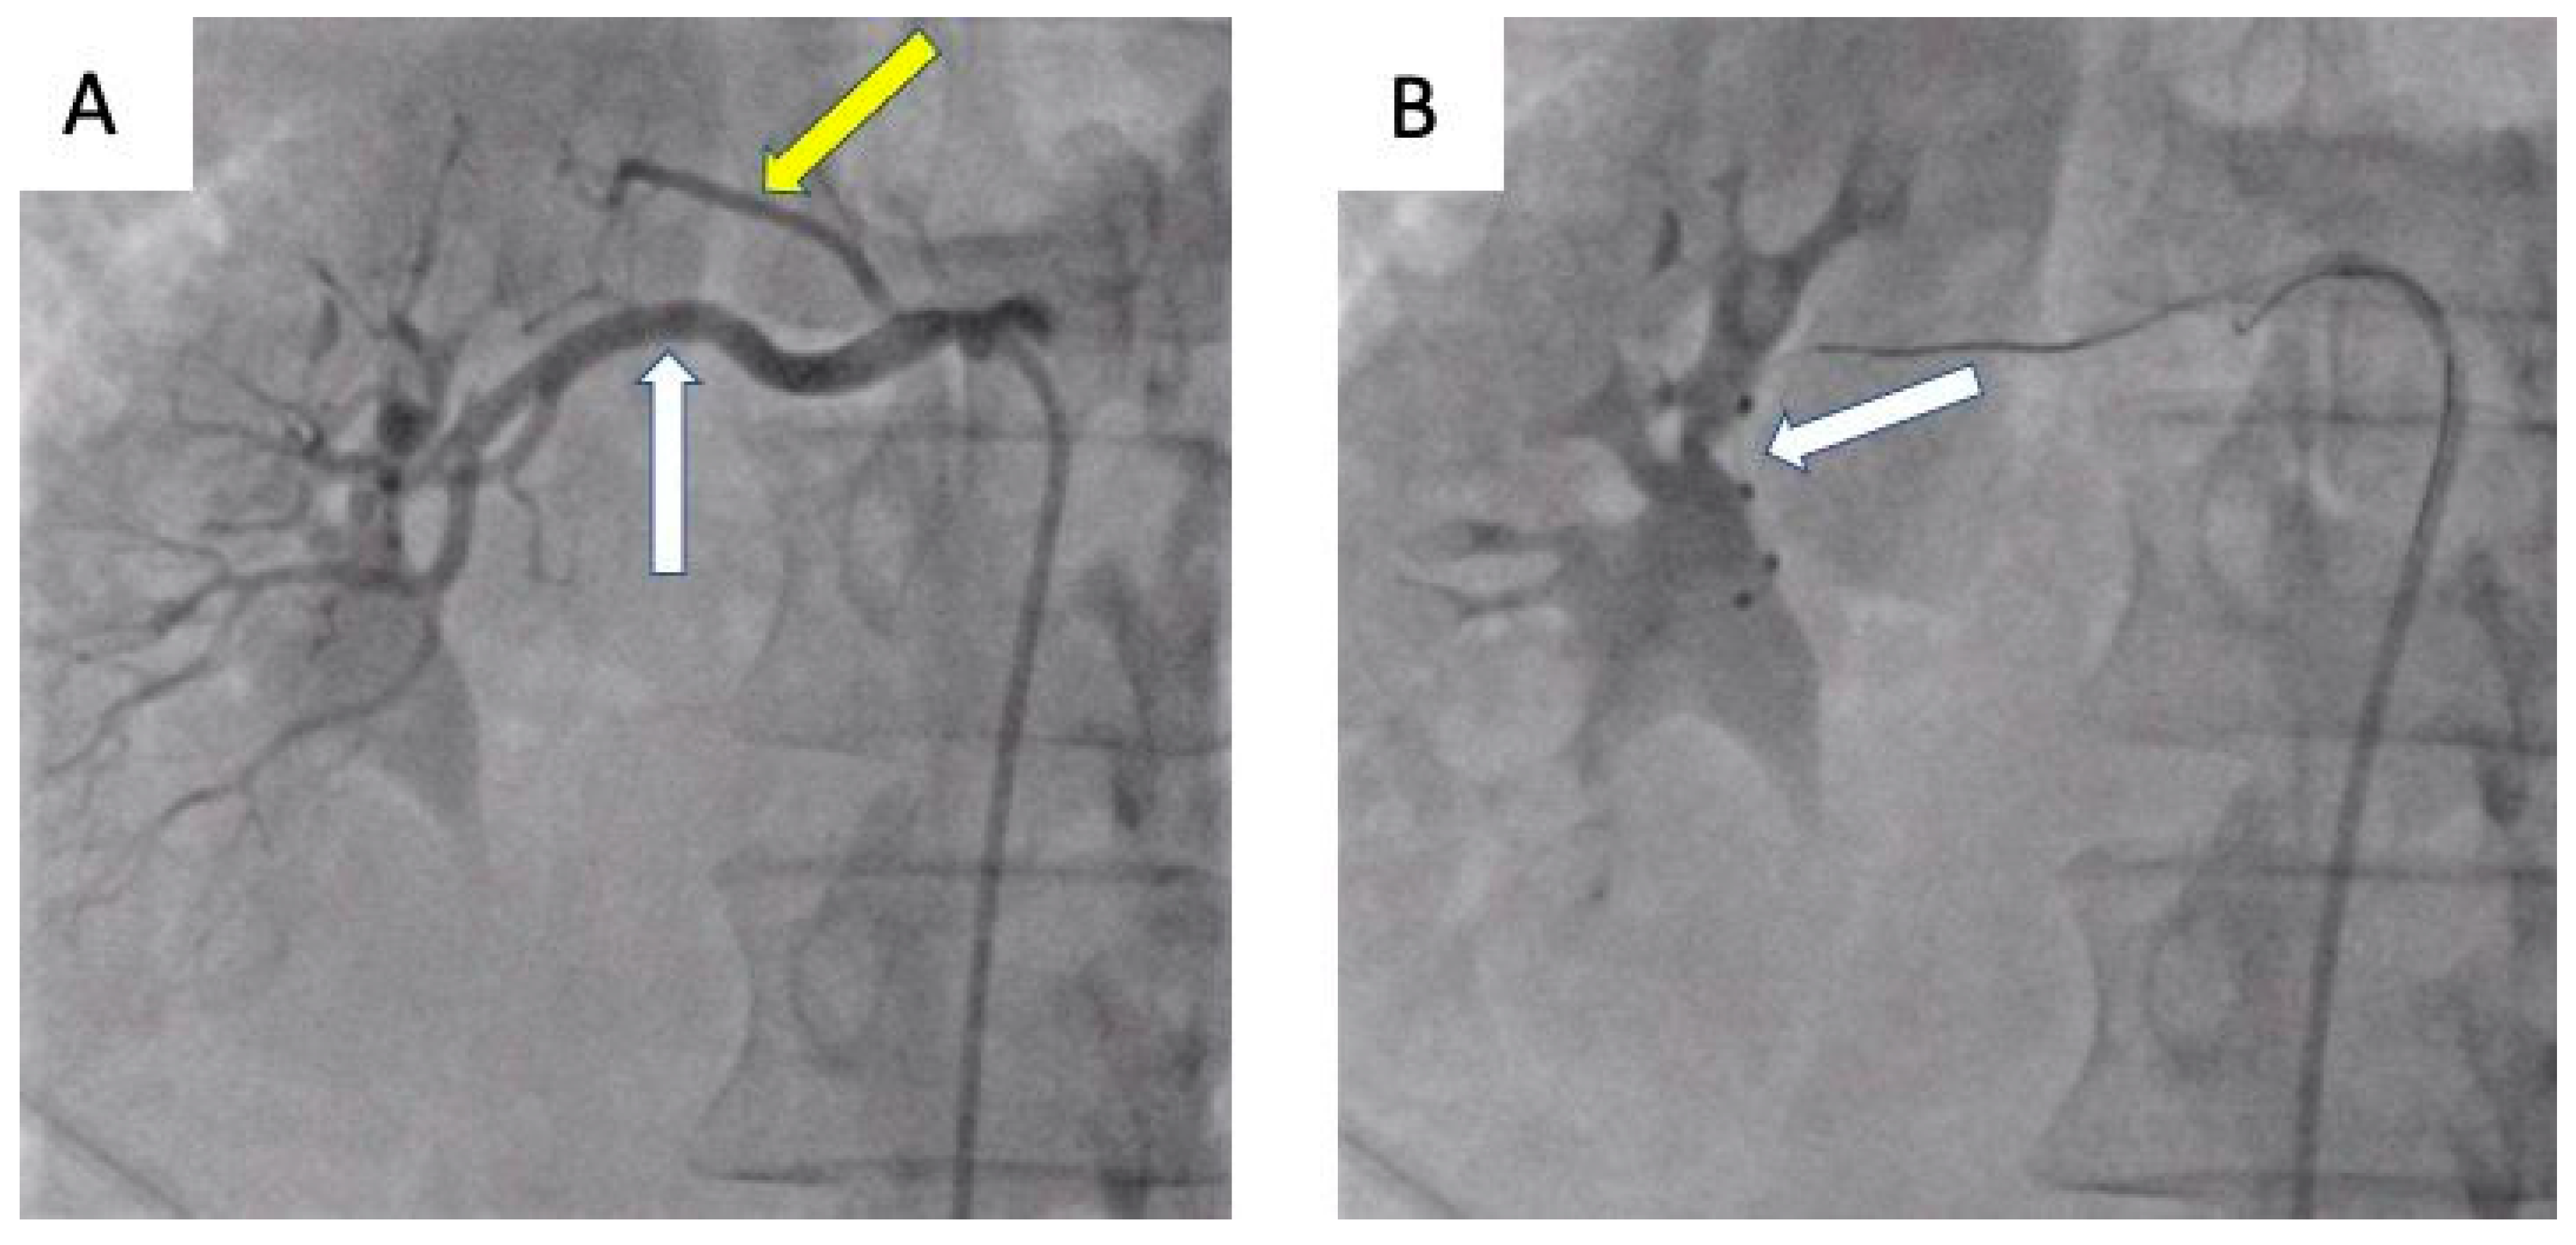

- Tokarek, T.; Rajtar-Salwa, R.; Rzeszutko, Ł.; Bartuś, S. Long-term benefit of redo sympathetic renal denervation in a patient with resistant hypertension. Postep. Kardiol. Inter. 2021, 17, 239–241. [Google Scholar] [CrossRef] [PubMed]

- Atas, H.; Durmus, E.; Sunbul, M.; Mutlu, B. Successful accessory renal artery denervation in a patient with resistant hypertension. Heart Views 2014, 15, 19–21. [Google Scholar] [PubMed]

- Bertoldi, L.; Latib, A.; Piraino, D.; Regazzoli, D.; Sticchi, A.; Pizzetti, G.; Camici, P.G.; Colombo, A. Renal denervation in a patient with two renal accessory arteries: A case report. Blood Press 2013, 22, 325–328. [Google Scholar] [CrossRef] [PubMed]

| de Leon-Martinez, Enrique Ponce et al. [45] | 55-yo man | Proximal bifurcation in the left RA and right ARA | RDN, RF ablation catheter (Symplicity Medtronic) | Five to two drugs | −29/9 after one month, −50/20 after two moths |